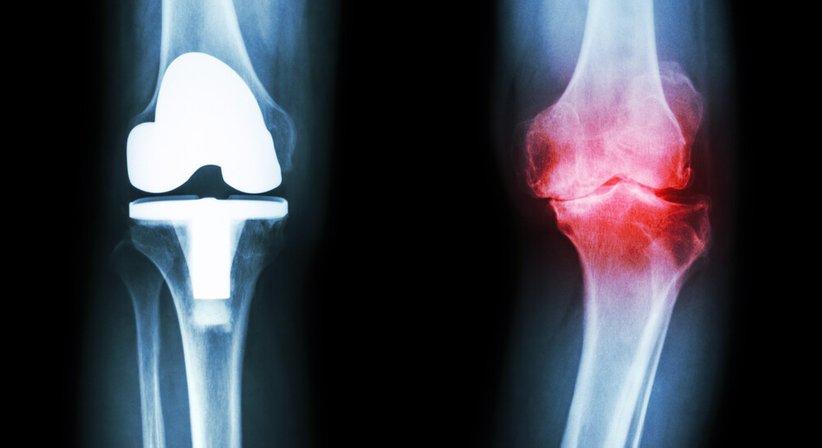

Besteht ab einem bestimmten Zeitpunkt im Krankheitsverlauf jedoch eine massive Arthrose vom Kniegelenk und sind konservative und arthroskopische/gelenkerhaltende Operationsmethoden nicht mehr wirksam, dann sollte die Implantation einer Knieprothese (Kniegelenkersatz, “künstliches Knie“) in Erwägung gezogen werden. Eine Knieprothese ersetzt das abgenützte Kniegelenk und ermöglicht es, Schmerzen und Bewegungseinschränkungen (weitestgehend) zu beseitigen und die Lebensqualität zu verbessern.

Abhängig davon, ob das Kniegelenk teilweise oder ganz ersetzt wird, wird grundsätzlich zwischen der Teilprothese (einseitige Schlittenprothese) und der Total-Endoprothese unterschieden (Knie-TEP). Bei einer Teilprothese wird während der Operation nur ein Teil vom Kniegelenk ersetzt, das restliche Gelenk (die gesunden Anteile) bleibt erhalten. Bei einer Total-Endoprothese wird das gesamte Gelenk durch die Prothese ersetzt. Jeder Prothesen-Typ ist in unterschiedlichen Formen, Größen und Ausführungen verfügbar; welche Prothese zum Einsatz kommt richtet sich nach verschiedenen Faktoren (Alter, Geschlecht, Körperbau, Gesundheitszustand, Knochenqualität, körperliche Aktivität etc.).